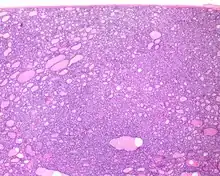

Several specific features must be identified for the tumor to be classified in this new category, while exclusion criteria should also be evaluated.

1) Encapsulated or partially encapsulated. The tumors are usually very well delimited or circumscribed, with the majority encapsulated, surrounded by a well formed fibrous connective tissue capsule.

2) Complete absence of invasion of any kind in a tumor that has been thoroughly and carefully evaluated with the whole capsule of the lesion sampled.

3) Predominantly follicular pattern of growth. Papillary structures should not be present. Further, solid, insular, or trabecular architecture must be <30% of the overall tumor for this category to still apply. Colloid (the material that thyroid follicular cells create) is easily identified throughout.

4) Must have the characteristic nuclear features of papillary thyroid carcinoma, although sometimes the features are patchy in distribution without all of the tumor showing those features. The nuclear features can be divided into three main categories:

- Nuclear size and shape: nuclear enlargement, nuclear elongation, and nuclear overlapping and crowding. Loss of nuclear polarity, with nuclei at the lumen, middle, or basal zone of the cells is also a helpful finding.

- Nuclear membrane irregularities: irregular nuclear contours, nuclear grooves and folds, "rat-bites" or demi-lune formations, and the presence of intranuclear cytoplasmic inclusions.

- Nuclear chromatin characteristics: nuclear chromatin clearing, often with condensation or margination along the nuclear membranes, resulting in accentuated nuclear margins, glassy nuclei, or fine, even delicate, powdery nuclear chromatin.

These features have been recently validated by an international group of practicing general surgical pathologists, showing a substantial interobserver agreement with applying a Nuclear Standardized Scoring System.[17]